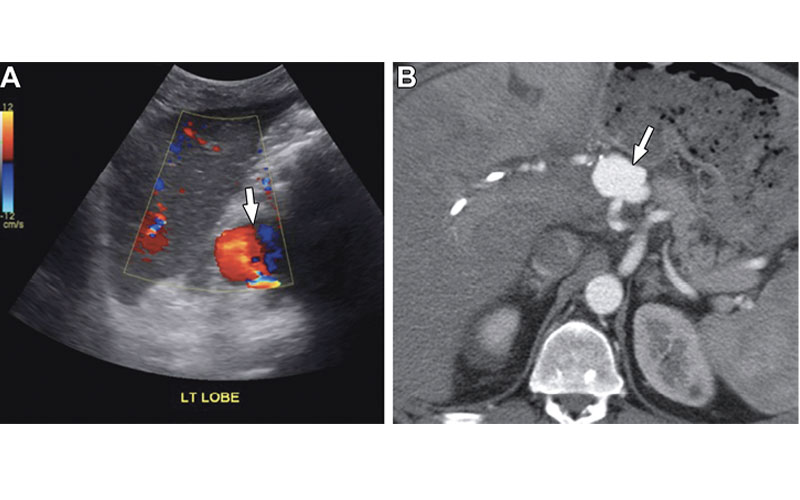

Hepatic artery pseudoaneurysm in a 54-year-old man with abdominal pain and elevated liver function test results 1 year after liver transplant. (A) Color Doppler US image shows a round vascular lesion (arrow) with yin-yang flow, consistent with a pseudoaneurysm. (B) CT angiography findings confirm a pseudoaneurysm (arrow) in the extrahepatic segment of the hepatic artery.

5. Hepatic artery pseudoaneurysm

These complications are rare but life threatening. Extrahepatic pseudoaneurysms are most often mycotic and they usually appear at the anastomosis or a site of prior angioplasty. Less common, intrahepatic pseudoaneurysms tend to occur at sites of prior biopsy or infection.